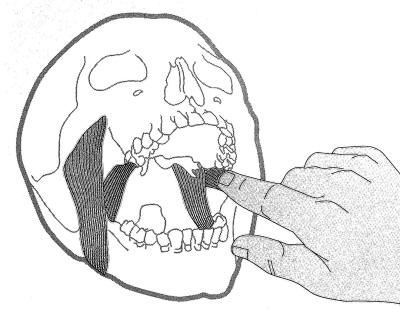

Palpación del haz inferior del pterigoideo externo: |

|

Para palpar el haz inferior del pterigoideo

externo, se realiza con el dedo meñique y se lo ubica por

delante del pilar anterior hasta la zona de tuberosidad. En

ese momento se desliza el dedo hacia atrás, con presión

moderada. El paciente puede sentir una molestia moderada,

hasta un dolor exquisito.

Si existe dolor intenso a la

palpación es señal de que el paciente presenta bruxismo. |